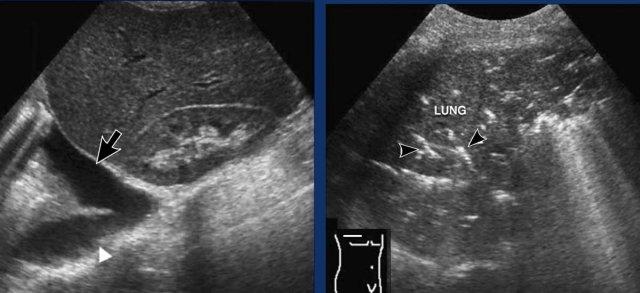

Các hình ảnh này thuộc về một phụ nữ 53 tuổi bị thuyên tắc phổi cấp tính, biểu hiện với các dấu hiệu lâm sàng của viêm túi mật.

Siêu âm qua gan cho thấy dịch màng phổi một bên (đầu mũi tên). Túi mật bình thường (không hiển thị). Trong quá trình siêu âm, bệnh nhân tiết lộ rằng các triệu chứng khởi phát ngay sau một chuyến bay liên lục địa.

Siêu âm ép phát hiện huyết khối trong tĩnh mạch đùi trái (mũi tên).

CT được thực hiện và phát hiện huyết khối trong động mạch thùy dưới phổi phải và tràn dịch màng phổi lượng ít.

Các hình ảnh sau đây liên quan đến một nam giới 81 tuổi bị thuyên tắc phổi cấp tính, ban đầu biểu hiện với các đặc điểm lâm sàng bắt chước viêm túi thừa đại tràng sigma.

- Siêu âm, sử dụng lách làm cửa sổ âm học, cho thấy đông đặc phổi kín đáo hoặc dịch màng phổi (đầu mũi tên), không phát hiện bất thường ổ bụng.

- Siêu âm phát hiện huyết khối (mũi tên) trong tĩnh mạch khoeo trái.

- Hình ảnh CT tái tạo MIP (hình chiếu cường độ tối đa) mặt phẳng coronal cho thấy huyết khối trong động mạch phổi thùy dưới trái (mũi tên vàng) và nhồi máu phổi (đầu mũi tên), tương ứng với hình ảnh đông đặc quan sát được trên siêu âm.